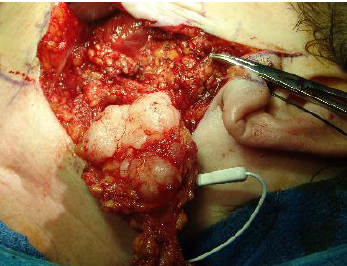

“blood soaked sponge” as surgical finding